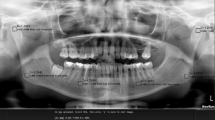

In dental diagnosis, radiographs are an essential adjuvant. To help with precise clinical evaluation, a variety of imaging techniques are frequently used, including intraoral periapical radiographs (IOPA), orthopantomograms (OPG), and cone-beam computed tomography (CBCT). Tools that can objectively identify changes in bone density and trabecular patterns are becoming more and more important as a result of the quick development of dental technology. Particularly in situations involving bone pathology, periodontal disease and systemic diseases affecting the bone. These tools provide invaluable assistance in early diagnosis and treatment planning thereby reducing the load on the radiologist. In this review, we seek to examine the diverse applications of fractal analysis in dentistry using radiographic images and the results of these applications.

The capacity of fractal geometry to quantify and analyze the irregular, fragmented forms of natural objects that are not amenable to measurement by conventional mathematical methods has resulted in the widespread adoption of fractal analysis across various disciplines, particularly in the medical domain, where fractal structures are prevalent [2, 3, 9]. The mandibular bone, characterized by its branching trabeculae, demonstrates statistical self-similarity. Consequently, the utilization of fractal geometry and the quantification of fractal dimensions (FD) can facilitate the assessment of the complexity inherent in the trabecular pattern and bone architecture [10]. Several prevalent applications where FA has demonstrated its utility include quantifying trabecular alterations following surgical and orthodontic interventions, assessing the surface roughness of implants, and evaluating the healing of periapical lesions subsequent to root canal therapy. Pictorial fractal analysis is likewise employed to assess histopathological specimens of premalignant and malignant tissue [9, 11]. Nevertheless, a more prevalent utilization of FA in dentistry involves the assessment of radiographic images to track alterations in the morphological configurations of the jawbones. Numerous investigations have been conducted primarily to examine the trabecular architecture of the mandible through the utilization of intraoral periapical radiographs, panoramic radiographs, and CBCT images. The most prevalent technique in fractal analysis is the box counting method developed by White and Rudolph for the processing of dental images [12]. Figure 2 depicts the applications of fractal analysis in various areas of dentistry.